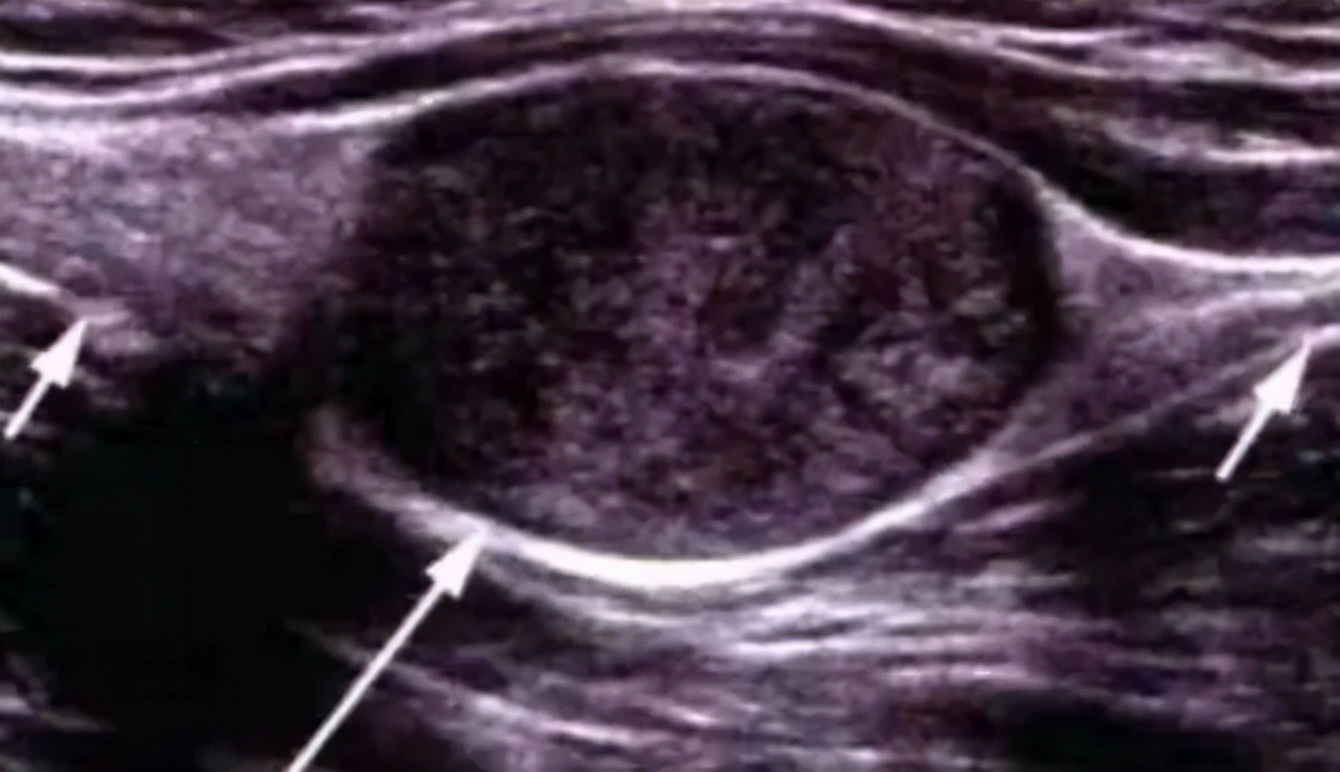

长在桡神经浅支的神经鞘瘤

瘤体和神经的关系

像不像穿在线上的“珍珠”?